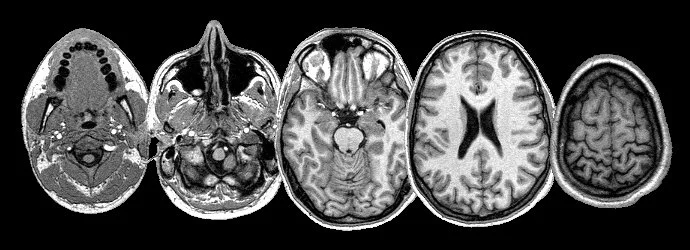

Magnetic resonance imaging (MRI) is a technique that uses a magnetic field and radio waves to create detailed images of the organs and tissues within your body.

Most MRI machines are large, tube-shaped magnets. When you lie inside an MRI machine, the magnetic field temporarily realigns hydrogen atoms in your body. Radio waves cause these aligned atoms to produce very faint signals, which are used to create cross-sectional MRI images — like slices in a loaf of bread.

MRI of the brain and spinal cord

MRI is the most frequently used imaging test of the brain and spinal cord. It’s often performed to help diagnose: